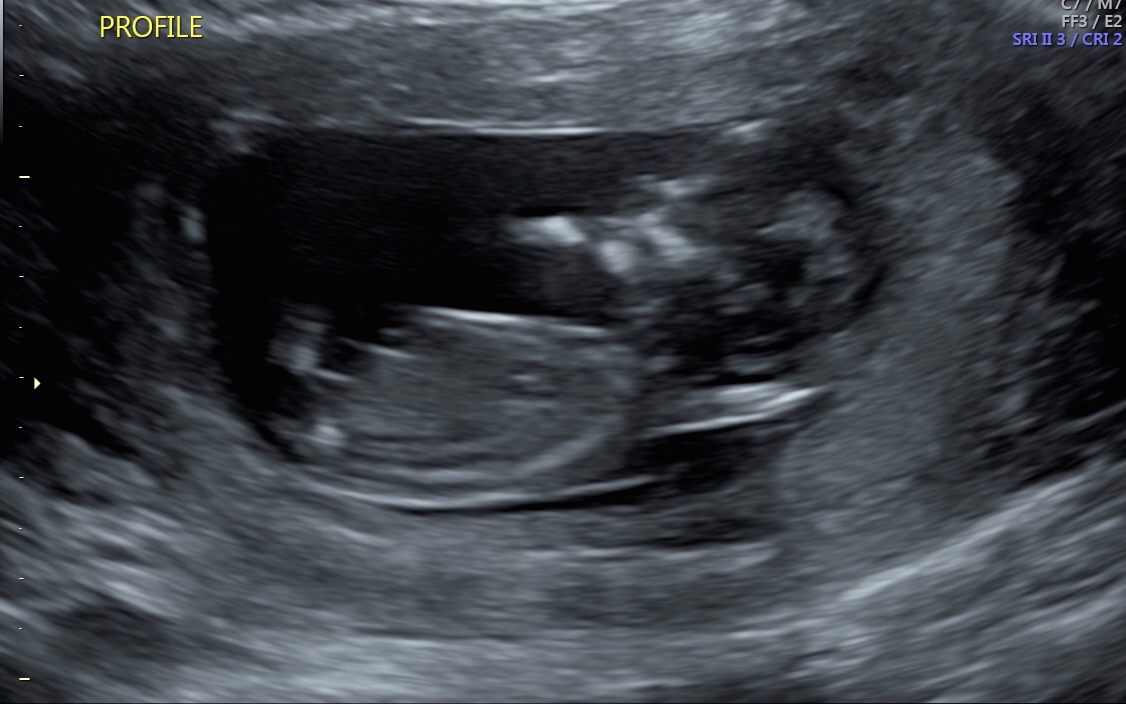

12w5d Any gender clues here? Attachment 39084Attachment 39085

Boy guess

Slight boy lean but not confident.